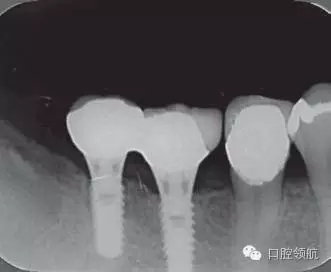

修復(fù)體安裝后的2003年1月復(fù)診時的X線片上,沒有發(fā)現(xiàn)種植體頸部有骨吸收現(xiàn)象,情況良好(圖2)。但是,2003年8月,因混合陶瓷樹脂部分修復(fù)體的破損而進(jìn)行再制作時,發(fā)現(xiàn)有輕度的咬合疼痛以及舌側(cè)頸部的牙齦有輕壓痛??趦?nèi)沒有觀察到該部位的牙齦紅腫。X線片可以觀察到(左下第6顆牙) 的種植體頸部有達(dá)到第4螺紋的骨吸收現(xiàn)象(圖3)。

圖2 沒有發(fā)現(xiàn)種植體頸部的骨吸收(2003年1月)